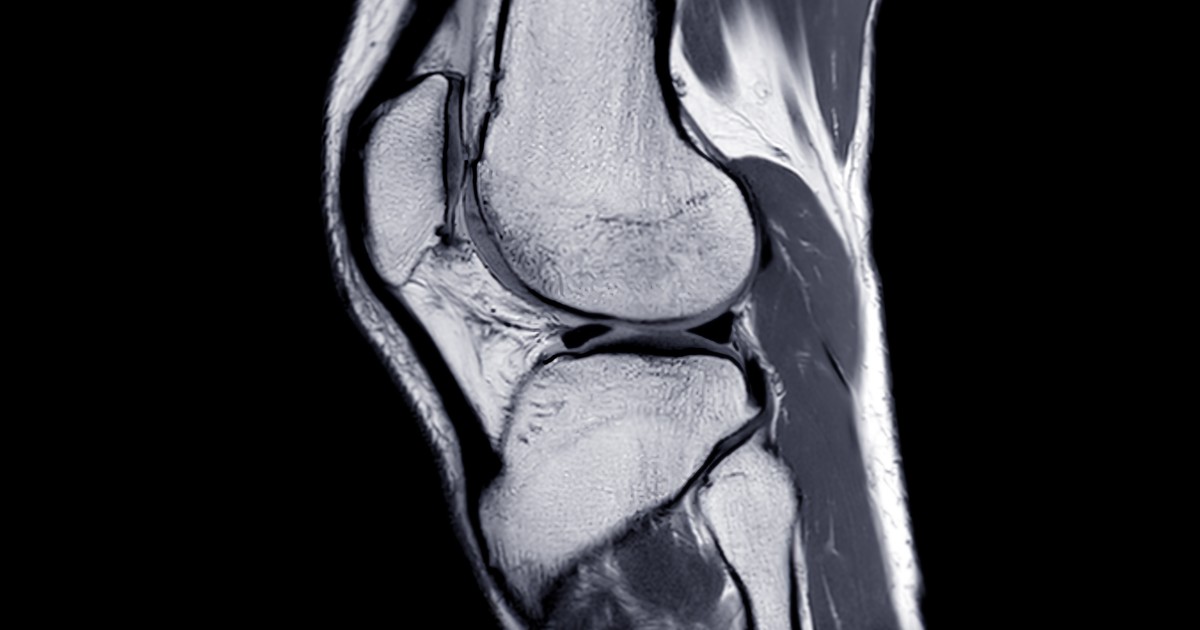

骨の損傷が疑われる場合、 X 線検査は骨折があるかどうかを判断するのに役立ちますが、医師が骨の打撲を検出するのには役立ちません。骨挫傷があるかどうかを確実に知る唯一の方法は、MRI スキャンを受けることです。これらの画像は、損傷が骨打撲より大きいかどうかを示す可能性があります。